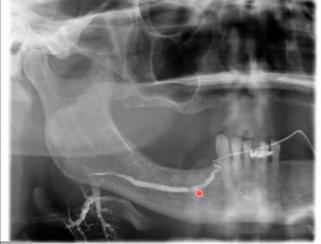

Describe what is happening in this sialography radiograph

• Narrowing of duct in left submandibular gland

• Showing complete stricture and closure of duct due to salivary stone

• No gland being contrasted due to stricture closure